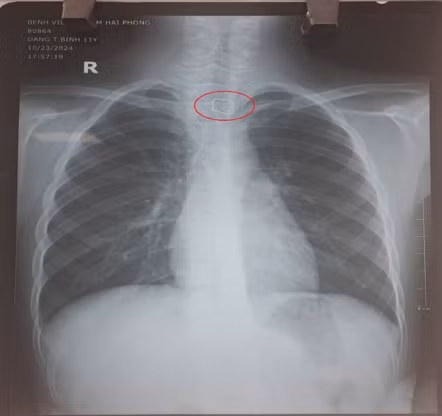

| Hình ảnh XQ dị vật trong đường tiêu hoá. Ảnh BVCC |

Qua kết quả cận lâm sàng, các bác sĩ phát hiện một vật cản quang, được xác định là dây kim loại nằm tại vị trí thực quản đoạn cổ. Ngay sau đó, bệnh nhi được gây mê và nội soi khẩn cấp, gắp chiếc hàm duy trì kích thước gần 3 cm ra khỏi đoạn 1/3 trên của thực quản một cách an toàn. Sau quá trình nội soi, sức khỏe của cháu bé đã ổn định.